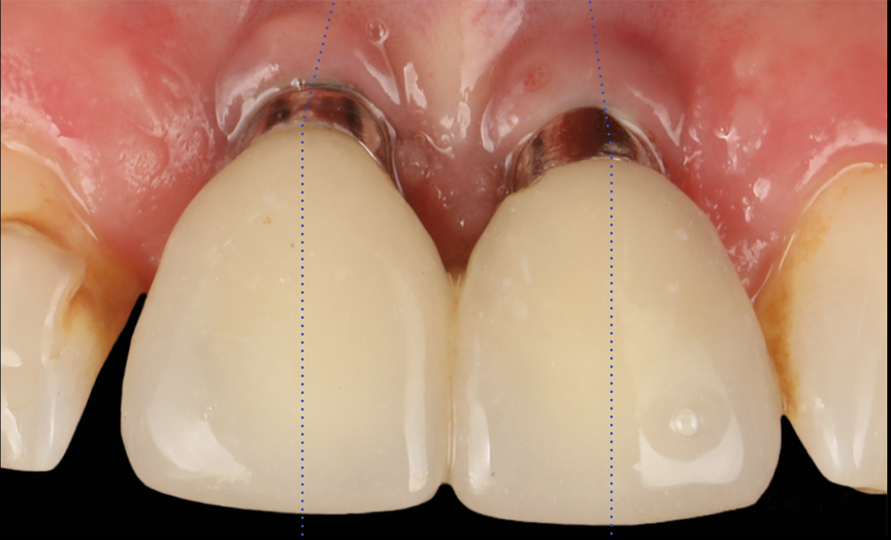

After 3 months of submerged healing, the operated area presented with limited keratinized mucosa on the buccal aspect (Figure 8). Therefore, a flap with two vertical incisions was designed starting from the palatal aspect of the two submerged implants. In addition, the mid-palatal portion of the flap was further extended toward the palatal aspect to obtain a roll flap that was de-epithelialized with a bur and eventually rolled to increase the interproximal soft tissue between the two implants (Figure 9). The flap was elevated in split-thickness fashion, with the soft tissue on top of the implants being removed to identify the cover screws (Figure 10). A substantial increase in soft-tissue thickness was observed at the buccal aspect of the implants compared to the first surgical procedure (Figure 11), when the implant fixtures were visible through a thin layer of connective tissue fibers adherent to the implant surfaces. The cover screws were removed, and temporary titanium abutments were connected.

The flap was closed using simple interrupted sutures (7-0 PGA, butterfly), with the mid-portion of the flap folded and rolled to increase the thickness and height of the interproximal soft tissue between the two implants (Figure 12). 3D-printed temporary crowns were adapted to the flap and delivered (Figure 13). Further modifications of the temporary crowns were performed between 1 month and 3 months, when the final ceramic restorations were delivered.

Fig 8. Surgical site after 3 months.

Figure 8

Fig 9. Flap design planning.

Fugure 9

Fig 12. Abutment connection and flap suturing.

Figure 12

Fig 13. Temporary crowns.

Figure 13